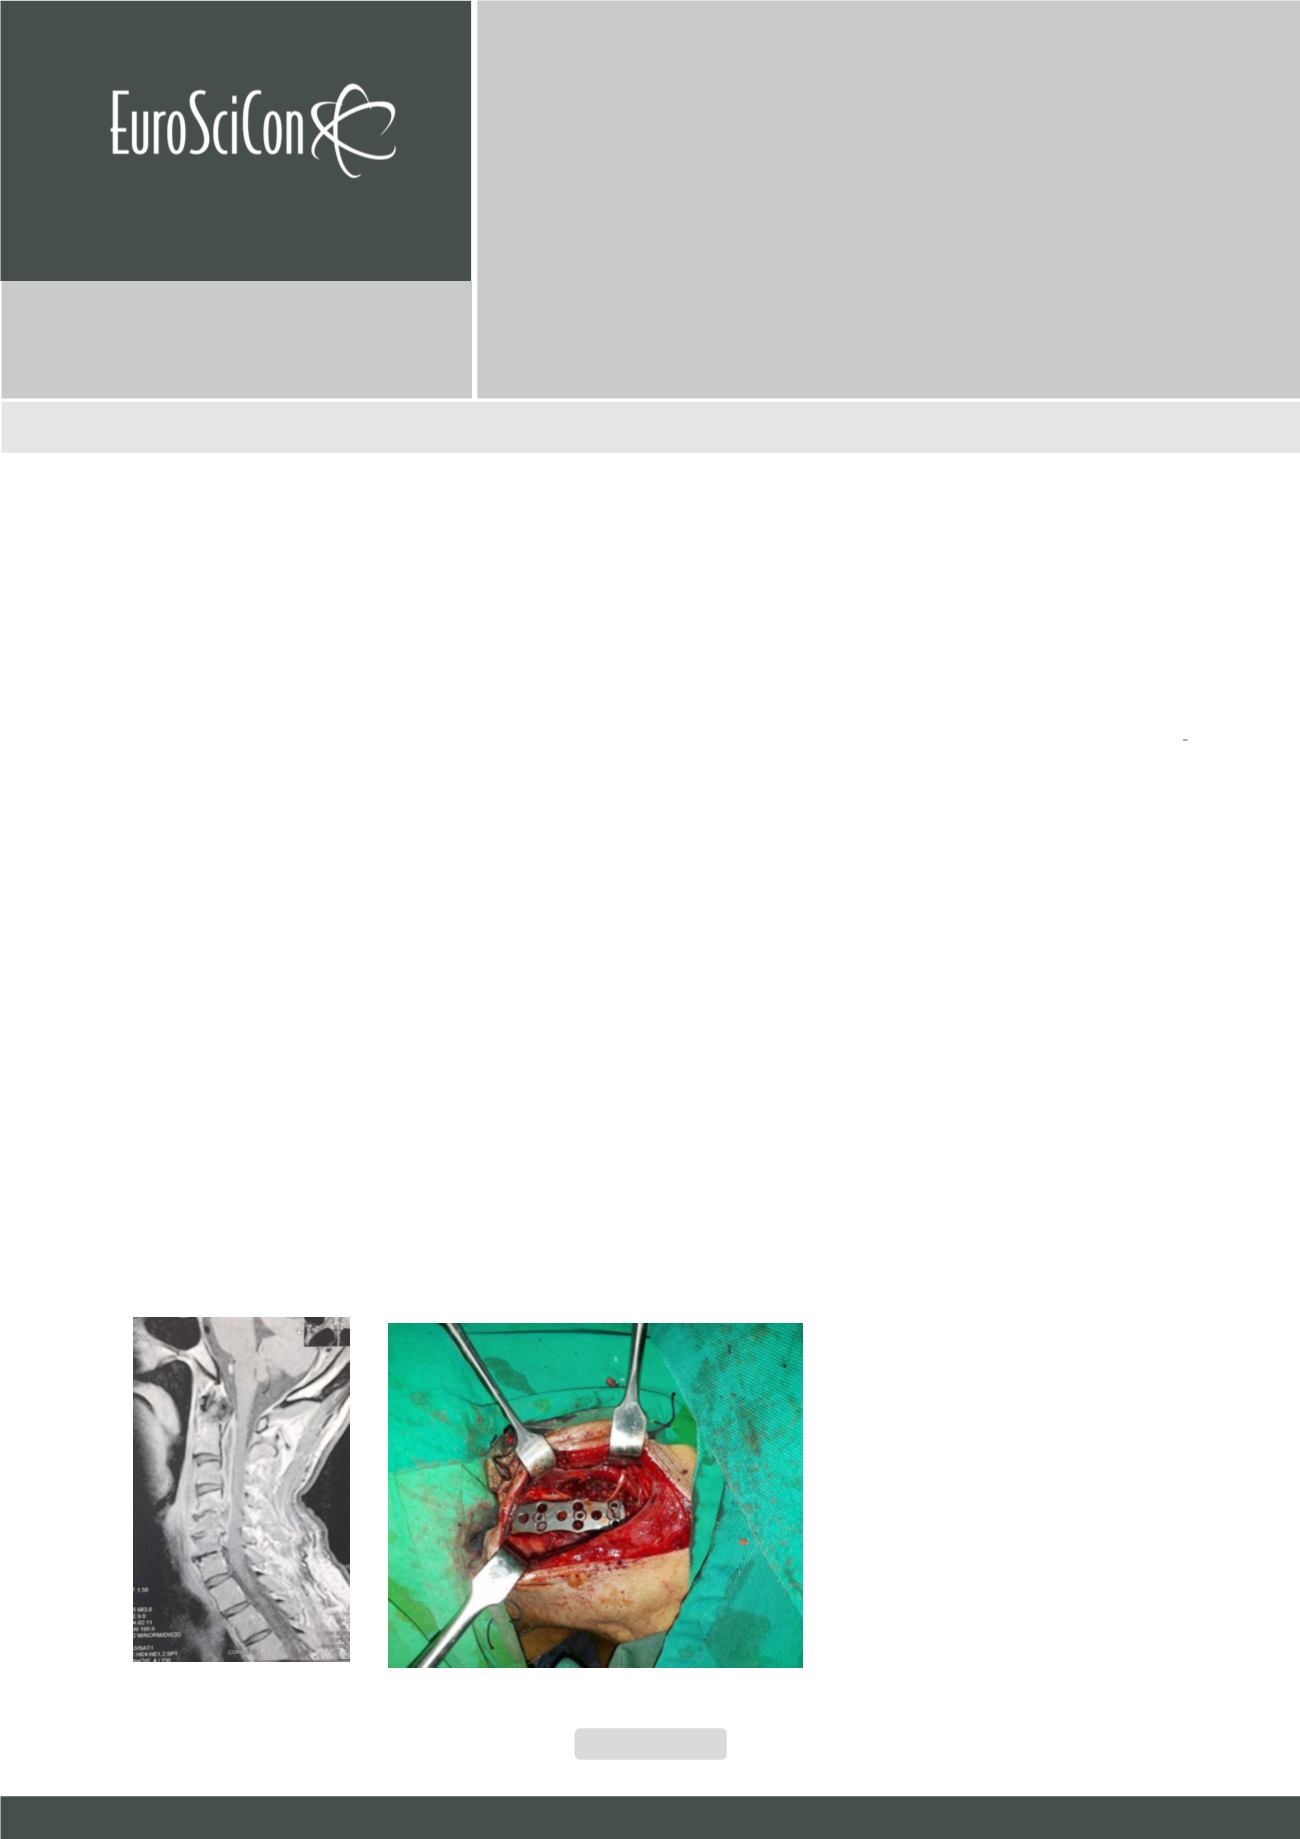

history of renal impairment and on medical treatment for about 4 years. Magnetic

Resonance imaging of the cervical spine, showed ventral cervical spinal cord

compression by an epidural abscess extending from the apex of dens to the level

of C5. Surgical intervention via anterior approach and corpectomy of the C4 and

C5, iliac crest graft with plate and screws fixation was done. About 3 months

after surgery, the patient markedly improved and was able to perform the usual

lifestyle activities.